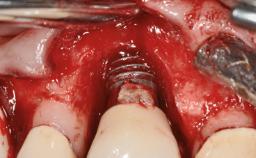

This case describes the ongoing management of a 64-year-old healthy, non-smoking female patient with erosive oral lichen planus (OLP) affecting the gingivae and the buccal and lingual mucosa. The peri-implant mucosa was also affected subsequent to implant placement. The patient had osseointegrated implants (four in the maxilla, four in the mandible) placed following extraction of hopeless teeth and a healing period. The patient had a history of OLP prior to implant placement and had been referred to an oral-medicine specialist for definitive diagnosis and treatment. She exhibited generalized oral mucosal involvement. Following a clinical assessment, biopsy, and blood tests, she was treated with topical corticosteroids. Systemic prednisolone was reserved for severe flare-ups. Amphotericin lozenges were used in combination with corticosteroid treatment to prevent the development of oral candidiasis.

# of Implants 8

Defining Characteristics Fully edentulous upper jaw to be rehabilitated with four or more implants